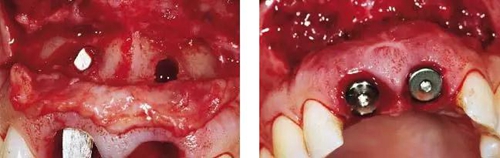

圖6、前庭溝半圓形切口,翻瓣后暴露左側(cè)和右側(cè)的骨缺損。

圖7、去除了肉芽組織和根尖感染組織,仔細(xì)沖洗后,可見雙側(cè)拔牙窩唇側(cè)骨壁有大面積缺損。

圖8、植入2顆Camlog平行壁螺紋種植體,扭矩達(dá)35Ncm。安放兩個(gè)粗直徑的愈合帽,防止軟組織退縮和凹陷。